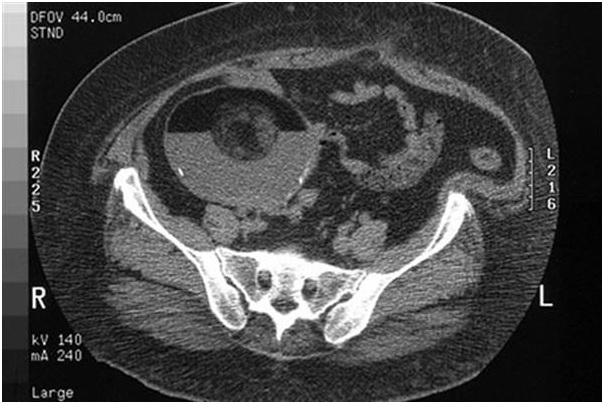

کیست در موئید تخمدان

کیست درموئید تخمدان